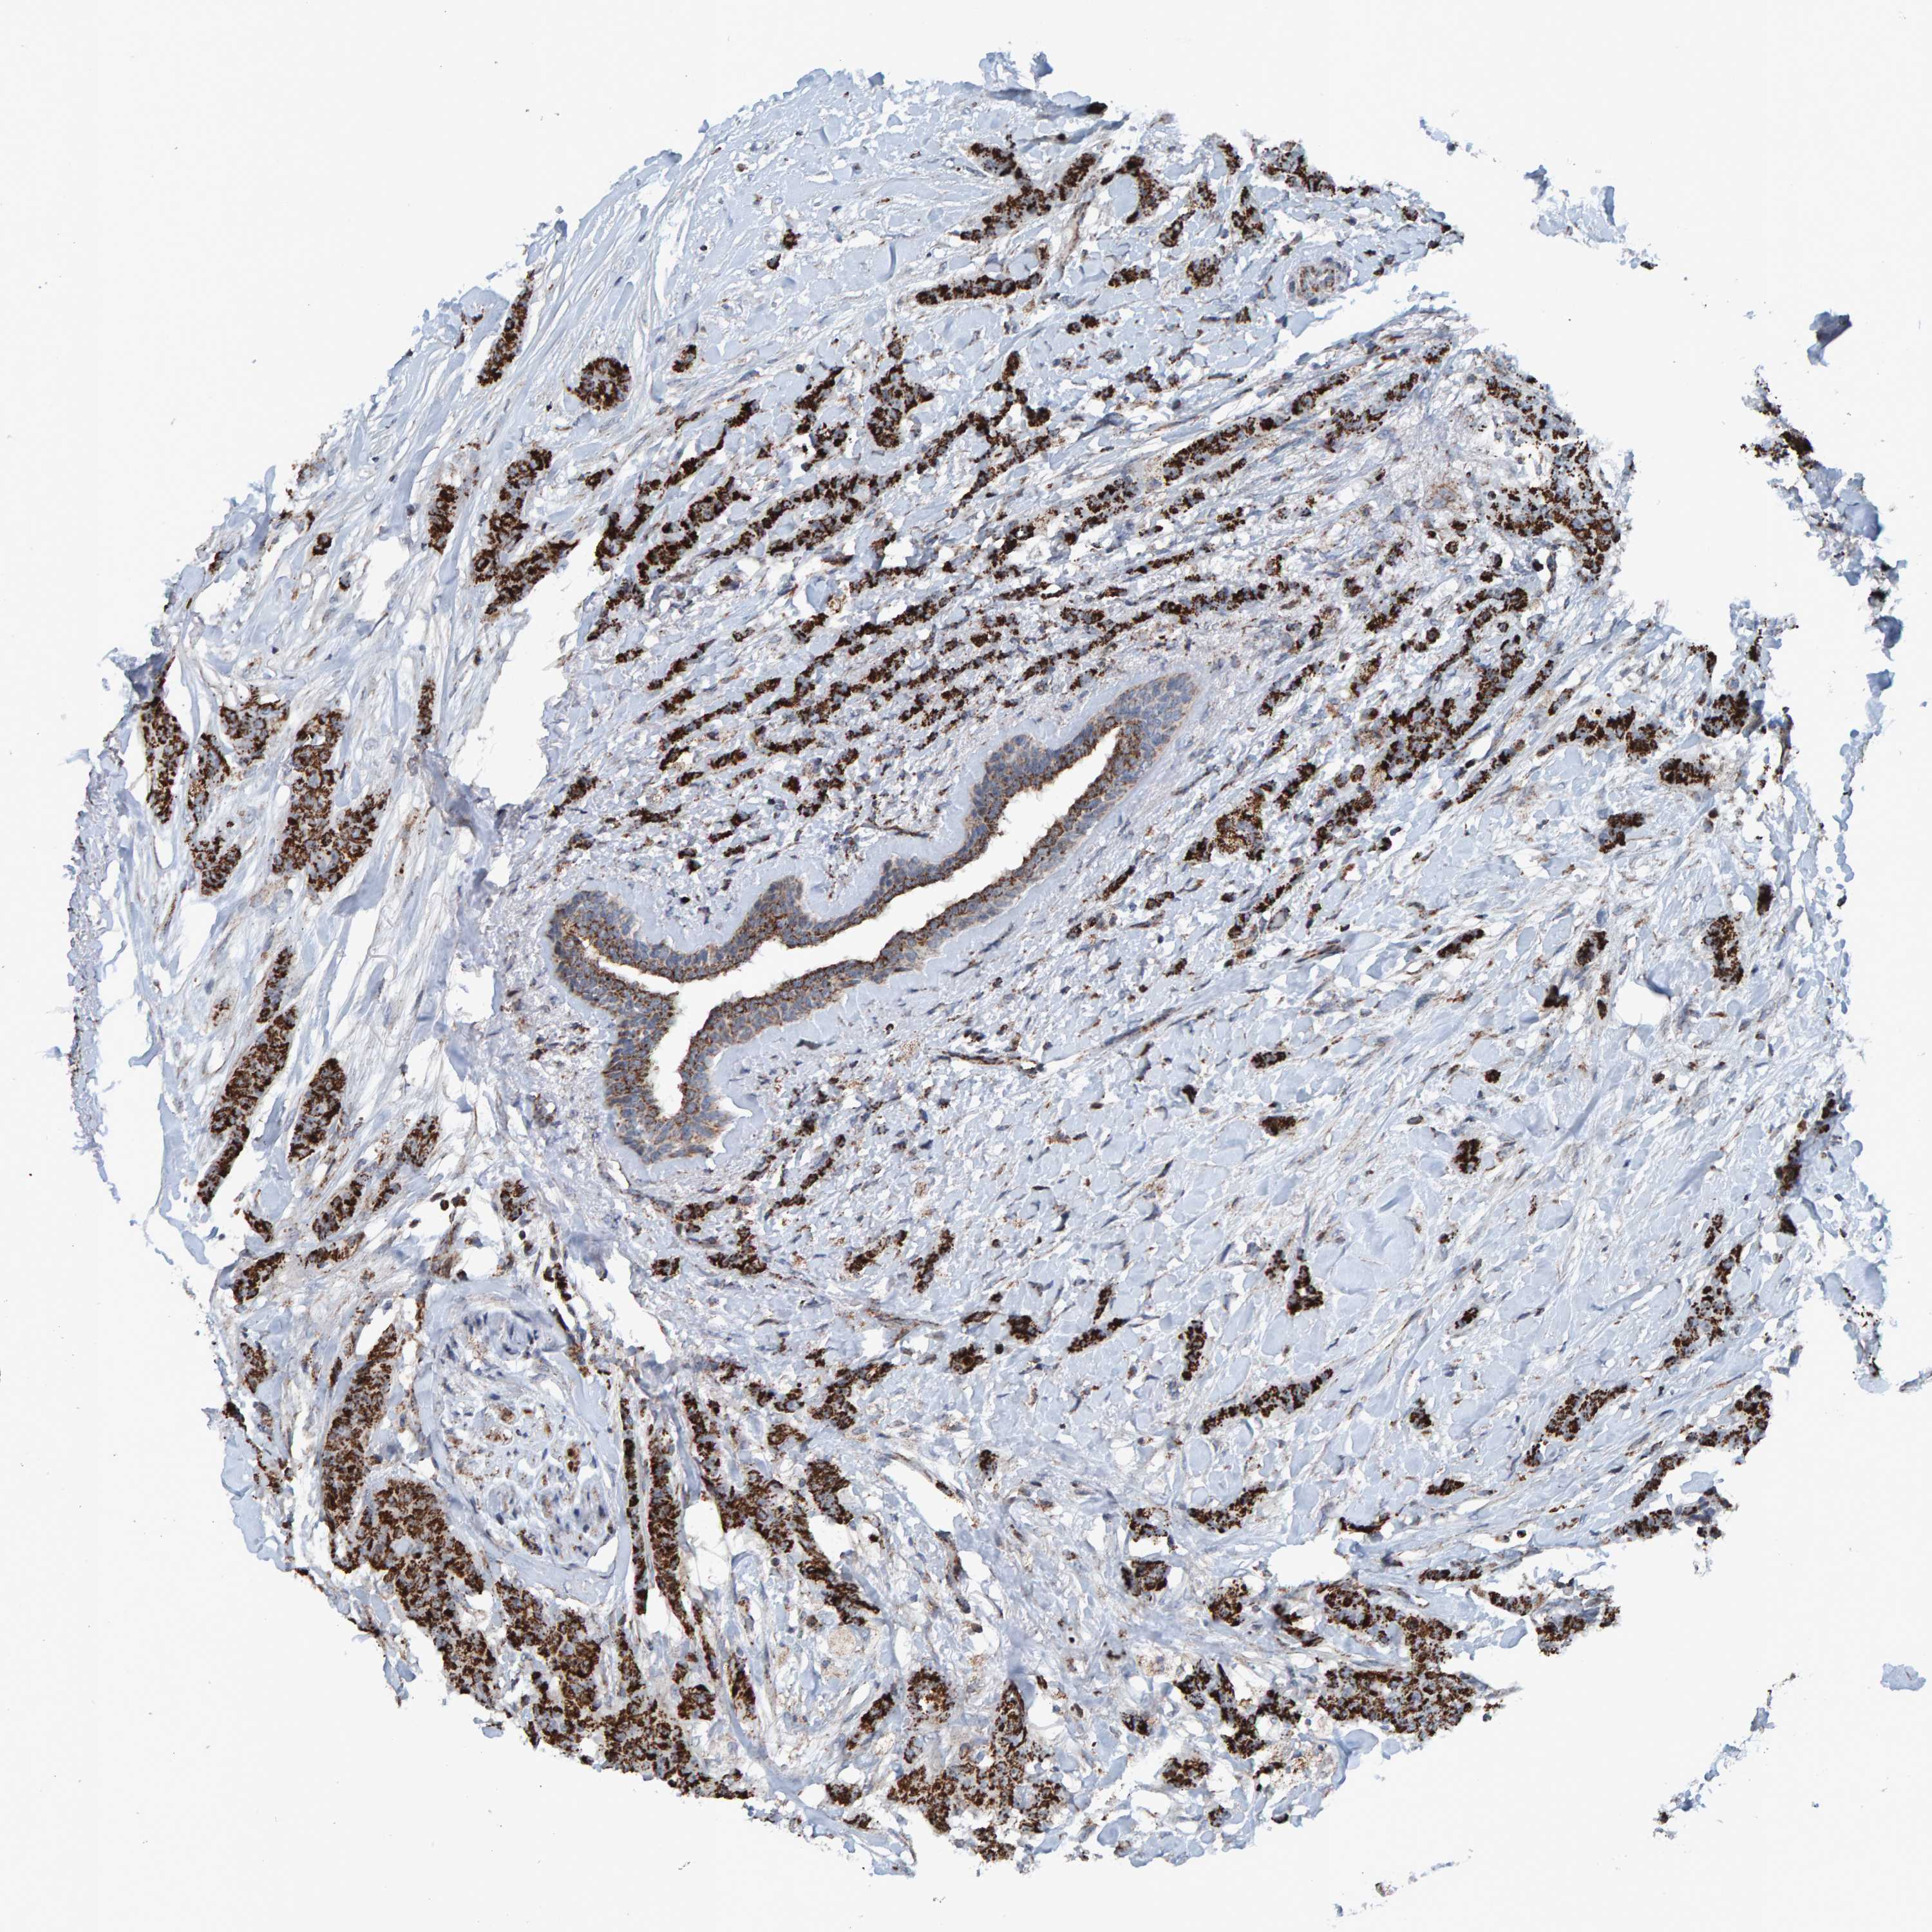

CANCER BREAST CANCER Show tissue menu

BRCA TCGA BRCA VALIDATION PROTEIN EXPRESSION

Breast cancer

Human cancer